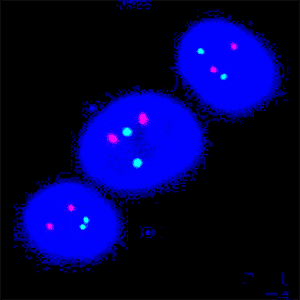

Figure 2

Same image as FIGURE 1, with identified nuclei and gene probes.